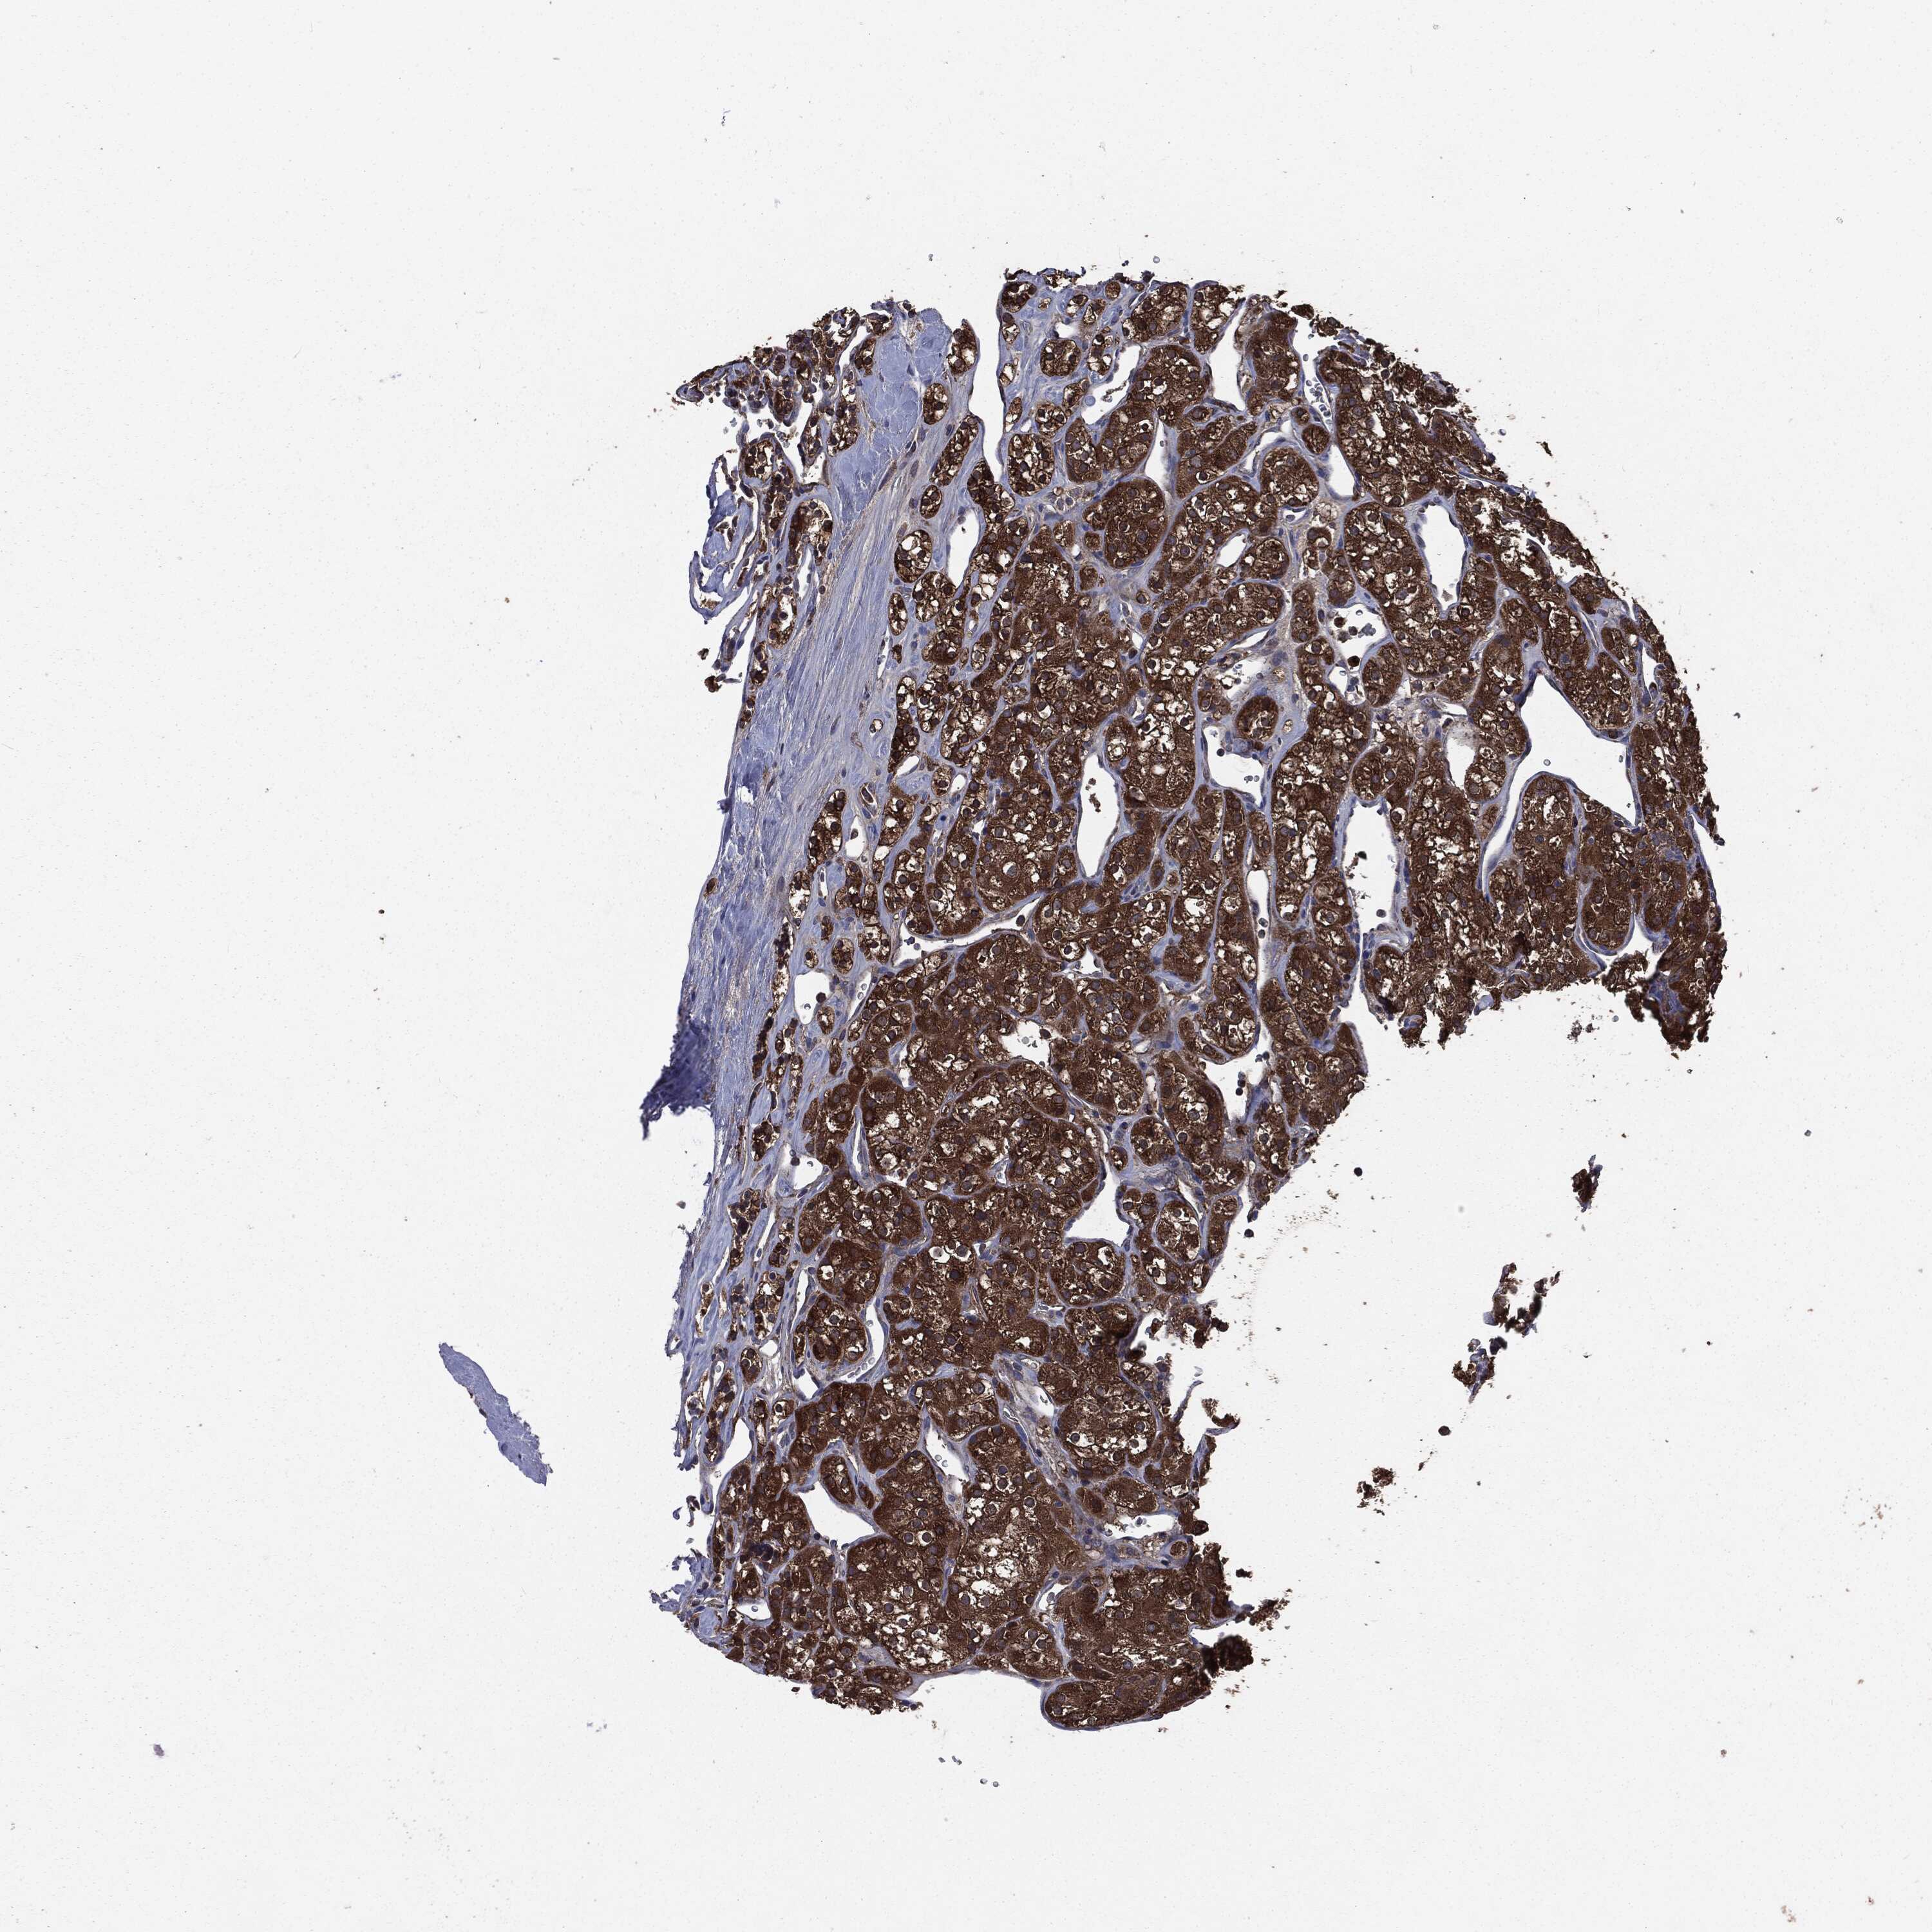

KIDNEY RENAL CLEAR CELL CARCINOMA (VALIDATION) - Interactive survival scatter ploti

The Survival Scatter plot shows the clinical status (i.e. dead or alive) for all individuals in the patient cohort, based on the same data that underlies the corresponding Kaplan-Meier plots. Patients that are alive at last time for follow-up are shown in blue and patients who have died during the study are shown in red.

The x-axis shows the expression levels (FPKM) of the investigated gene in the tumor tissue at the time of diagnosis. The y-axis shows the follow-up time after diagnosis (years). Both axes are complimented with kernel density curves demonstrating the data density over the axes. The top density plot shows the expression levels (FPKM) distribution among dead (red) and alive patients (blue). The right density plot shows the data density of the survived years of dead patients with high and low expression levels respectively, stratified using the cutoff indicated by the vertical dashed line through the Survival Scatter plot. This cutoff is automatically defined based on the FPKM cutoff that minimizes the p-score. The cutoff can be changed by dragging the vertical line or by entering a cutoff value in the square labeled "Current cut-off".

Under the Survival Scatter plot the p-score landscape (black curve; left axis) is shown together with dead median separation (red curve; right axis). Dead median separation is the difference in median mRNA expression between patients who have died with high and low expression, respectively. It is calculated as follows: median FPKM expression of dead patients with high expression - median FPKM expression of dead patients with low expression. This is intended to aid the user in visually exploring custom cutoffs and the associated p-scores and dead median separation.

Individual patient data is displayed and can be filtered by clicking on one or more of the category buttons on the top of the page. Categories describing expression level and patient information include: high, low, alive, dead, female, male and tumor stages. The scale of the x-axis can be toggled between linear and log-scale by clicking on the "x log" button. Mouse-over function shows TCGA ID, patient information and mRNA expression (FPKM) for each patient.

& Survival analysisi

Kaplan-Meier plots summarize results from analysis of correlation between mRNA expression level and patient survival. Patients were divided based on level of expression into one of the two groups "low" (under cut off) or "high" (over cut off). X-axis shows time for survival (years) and y-axis shows the probability of survival, where 1.0 corresponds to 100 percent.

MAPK6 is not prognostic in Kidney Renal Clear Cell Carcinoma (validation)

Best expression cut offi

: 15.27

Average pTPM 16.7

Number of samples 100